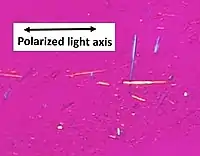

A definitive diagnosis of gout is based upon the identification of monosodium urate crystals in synovial fluid or a tophus.[6] All synovial fluid samples obtained from undiagnosed inflamed joints by arthrocentesis should be examined for these crystals.[7] Under polarized light microscopy, they have a needle-like morphology and strong negative birefringence. This test is difficult to perform and requires a trained observer.[52] The fluid must be examined relatively soon after aspiration, as temperature and pH affect solubility.[7]

Light microscopy of a touch preparation of a gout tophus, showing needle-shaped crystals.

Light microscopy of a touch preparation of a gout tophus, showing needle-shaped crystals. Uric acid crystals in polarized light, showing negative birefringence, with yellow color when aligned parallel to the axis of the red compensator, and blue when aligned perpendicularly to it.[59]

Uric acid crystals in polarized light, showing negative birefringence, with yellow color when aligned parallel to the axis of the red compensator, and blue when aligned perpendicularly to it.[59] In contrast, CPPD (pseudogout) displays rhombus-shaped crystals with positive birefringence.